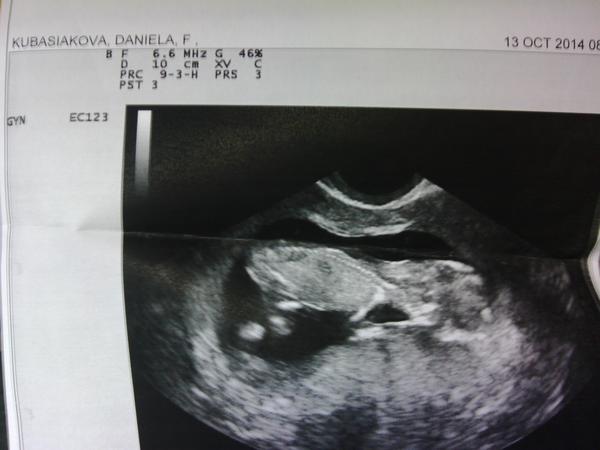

Ahojte kocky.....idem vam predstavit nasho chrobáčika....včera sme mali kontrolu....všetko je ok meriame 2,2cm 🙂

@acerka11 jeeeeej tak ten je krásny....tak len tak ďalej...nech vám krásne rastie 😀

@acerka11 Krásne babuliatko 😵 Držkajte sa 😉

A vy dve @veeeron @seraa pekne poosahavajte obrazovku, nech sa aj na vás ''prilepí'' 😉 Ja mám kontrolu v pondelok, tak ja pridám foto neskôr, inak už sa citim lepšie, ale tie prvé tt to bolo 😖 😝 Držím vám palce, aby ste nás do Vianoc pekne nasledovali 😉